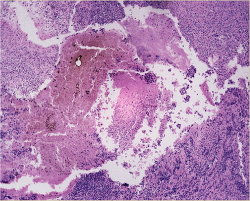

Figure. No caption a... - Click to enlarge in new windowFigure. No caption available.